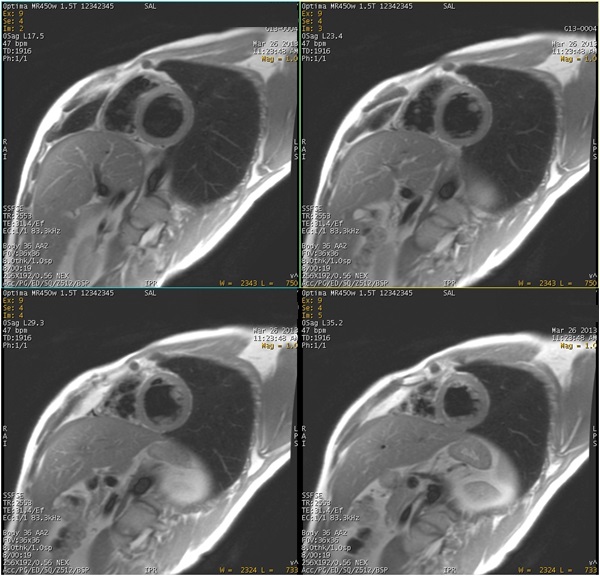

Figure 1. Image acquired with Diastolic Trigger Delay

- Diastolic and Systolic Trigger Delays are available. For optimum image quality and very good blood suppression in the ventricles, select Trigger Delay: Diastolic.